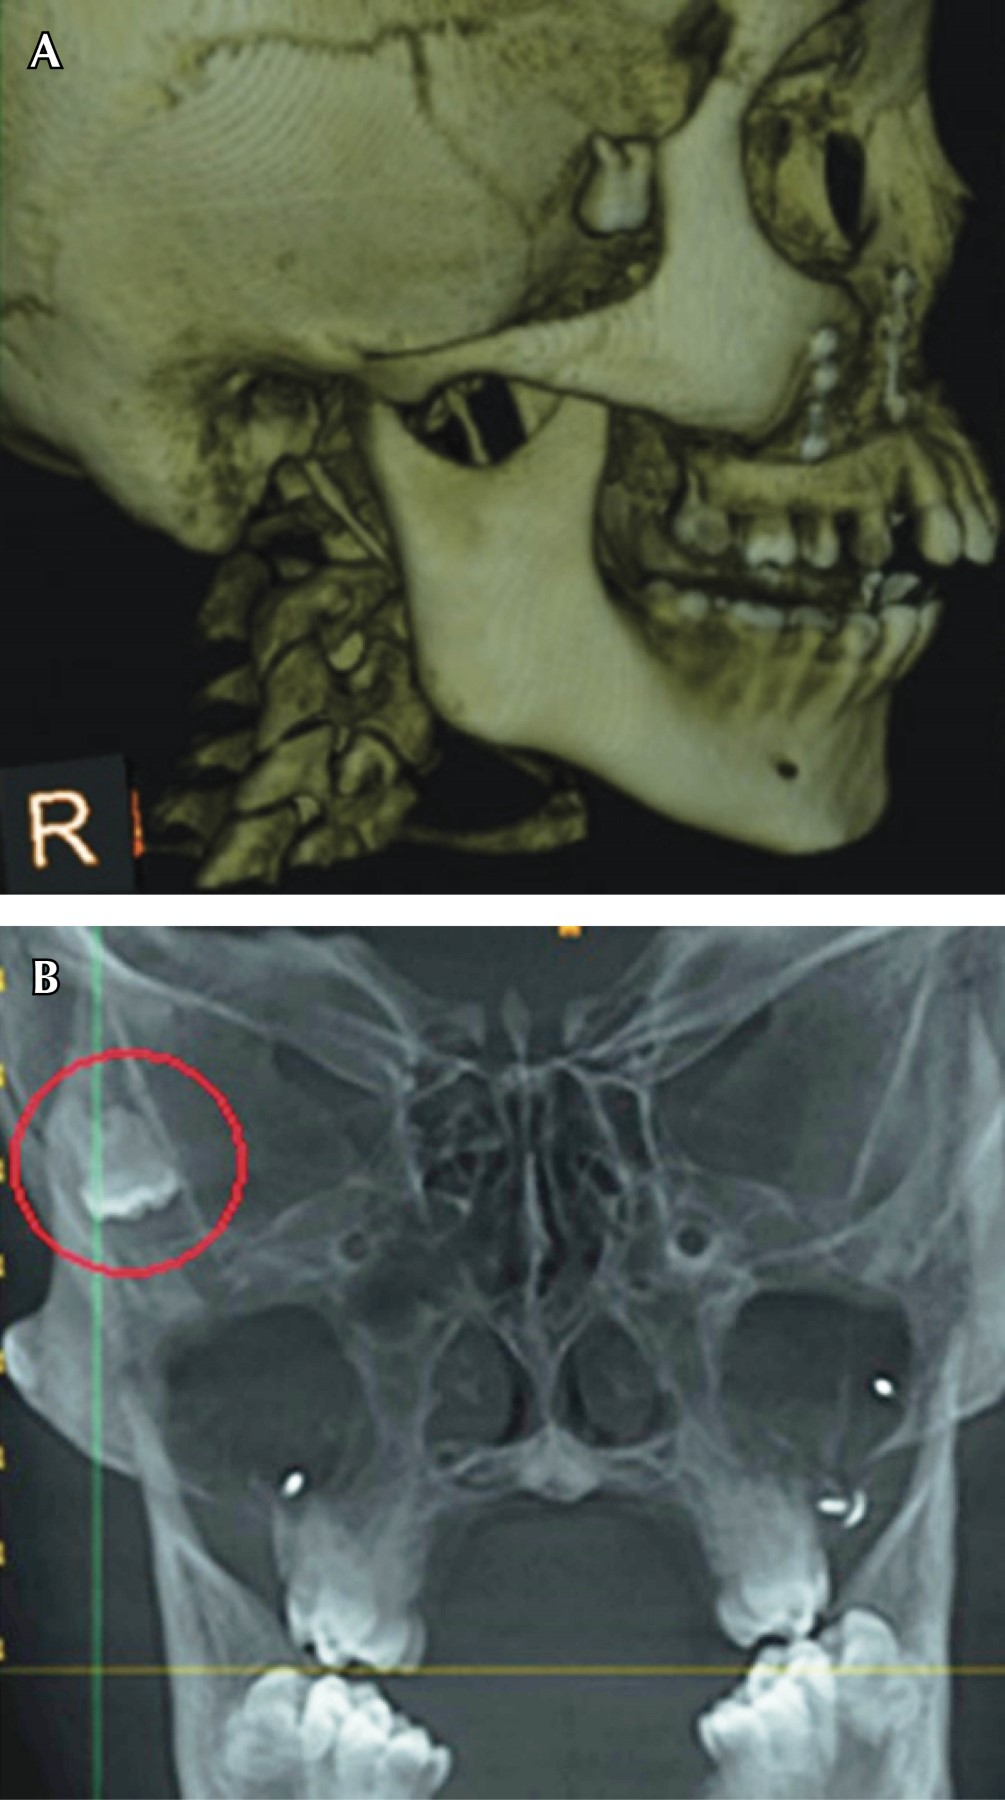

La recuperación de la unidad dentaria desplazada puede ser mediante un abordaje intraoral como fue expresado anteriormente, o extraoral como lo presenta Nadeem A y su equipo en el estudio denominado: A rare case of mandibular third molar displaced into submandibular space: A complication of mandibular third molar extraction10 en el cual mencionan el caso de un paciente masculino de 44 años de edad, en donde en una cirugía anterior ocurrió el desplazamiento del tercer molar inferior izquierdo, al realizar los estudios radiográficos y una tomografía computarizada, se dio a conocer la ubicación exacta del tercer molar el cual se encontró en la zona submandibular (Figuras 5 y 6); el abordaje fue realizado mediante un colgajo lingual, bucal y una incisión en la zona submandibular, ya que la unidad dentaria se encontraba muy profunda, sin embargo, con buena iluminación lograron encontrar la unidad dentaria y con una cureta se pudo traccionar el molar hacia el exterior (Figura 7). A diferencia de los casos de desplazamiento de terceros molares, en los cuales el único abordaje posible es de manera extrabucal, como expresan Shruthi TM y colegas en el estudio tipo reporte de caso: Removal of Displaced Maxillary Third Molar Using Modified Gillie's Temporal Approach11 donde presentan a un paciente femenino de 26 años de edad cuyo tercer molar superior derecho fue desplazado durante la osteotomía del hueso maxilar Le Fort 1, para el reposicionamiento del hueso maxilar por aumento de la dimensión vertical; el tercer molar fue desplazado hacia los tejidos más profundos y no se podía palpar, en la misma cirugía se intentó recuperar el tercer molar a través de la incisión intraoral que ya se había realizado para la osteotomía, pero no se tuvo éxito. Se indicó la realización de una tomografía computarizada lo cual reveló que el tercer molar fue desplazado hacia la fosa infratemporal (Figura 8). Por su ubicación se decidió realizar un abordaje extraoral mediante un "abordaje temporal de Gillies modificado", el tercer molar fue encontrado y recuperado con éxito. De la misma manera, Oliveira MMM y colaboradores en el estudio Third Molar Displacement into Submandibular Space,12 reportan el caso de un paciente masculino de 21 años quien durante la cirugía para la extracción del tercer molar inferior izquierdo experimentó el desplazamiento de un fragmento de la unidad dentaria. Durante la cirugía el operador intentó recuperar el fragmento pero no tuvo éxito. Se indicó la realización de una tomografía computarizada Cone Beam, para la revisión y ubicación del mismo, el cual se encontró en el espacio submandibular (Figura 9). Para la recuperación del fragmento se decidió realizar un acceso extraoral en la región submandibular bajo anestesia general, la unidad dentaria se pudo recuperar con éxito (Figura 10).

Figura 5

Figura 6

Figura 7

Figura 8